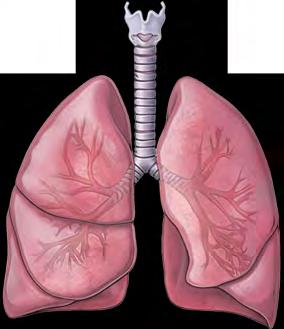

організмі людини виокремлюють такі фізіологічні системи органів: опорно-рухова, яка забезпечує формування структури тіла, механічний захист органів, здатність

до різноманітних рухів; дихальна, яка постачає до організму кисень та

кровоносна, яка вможливлює транспортування різноманітних речовин по організму, а також бере участь

для побудови складників, частина розщеплюється з вивільненням енергії для забезпечення протікання різноманітних процесів. Дихальна система постачає потрібний для цього

(іл. 56 ). Опорно-рухова система містить кістки й скелетні м’язи. Вона виконує захисну, опорну, рухову, метаболічну, кровотворну й терморегуляційну функції (іл. 58).

Грудна клітка

захищає

серце

й легені